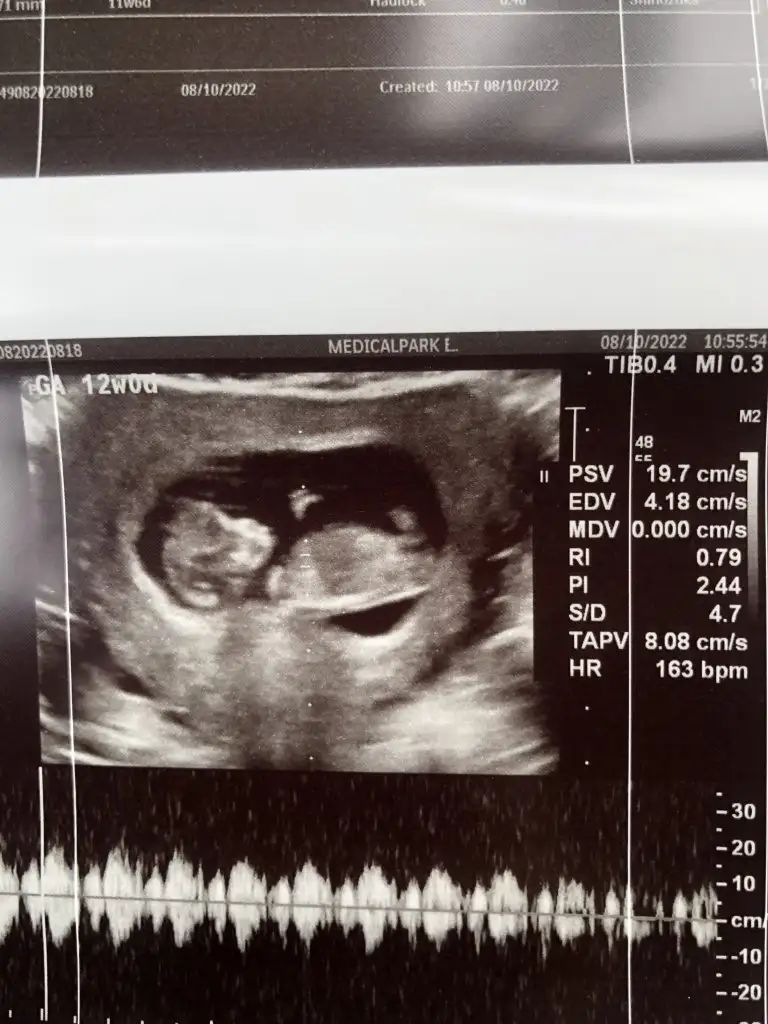

Kiz bebek ama net degilim çünkü goremiyorum istdigim acidanmerhaba 12+0 tahmin edebilir misiniz?Derinvebebekleri

Teşekkür ederimKiz bebek ama net degilim çünkü goremiyorum istdigim acidan

Bana da yorum yapabilir misinizErkek bu adim gibi eminim

Erkeğe benzettim nubunu cnm benim büyük oğlumunkide böyleydiEki Görüntüle 3144739

Dün Dr'a gittik kıza benzetti bakalım hayırlısıErkeğe benzettim nubunu cnm benim büyük oğlumunkide böyleydi

Çoğunluk erkek diyor ama Dr kız diyor :)Dün Dr'a gittik kıza benzetti bakalım hayırlısı